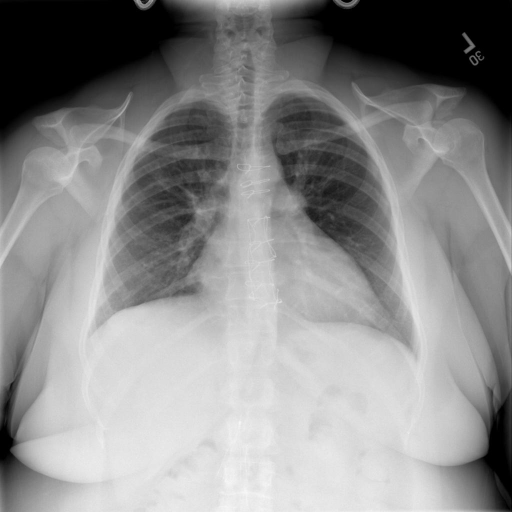

## 本文贡献  - 借助ChatGPT以及公开的数据集,我们构造了一个`X光影像-诊断报告`对的医学多模态数据集; - 我们将构建的中文胸部X光片诊断数据集在[VisualGLM-6B](https://github.com/THUDM/VisualGLM-6B)进行微调训练,并开放了部分训练权重用于学术研究; ## 数据集 - [MIMIC-CXR](https://physionet.org/content/mimic-cxr-jpg/2.0.0/)是一个公开可用的胸部X光片数据集,包括377,110张图像和227,827个相关报告。 - [OpenI](https://openi.nlm.nih.gov/faq#collection)是一个来自印第安纳大学医院的胸部X光片数据集,包括6,459张图像和3,955个报告。 在上述工作中,报告信息都为非结构化的,不利于科学研究。为了生成合理的医学报告,我们对两个数据集进行了预处理,并最终得到了可以用于训练的**英文报告**。除此之外,为了更好的支持中文社区发展,借助ChatGPT的能力,我们将英文报告进行了中文翻译,并最终形成了可用于训练的数据集。 |数据集|数量|下载链接| |:-|:-|:-| |MIMIC-CXR-zh|-|-| |OpenI-zh|6,423|[诊疗报告(英文)](./data/openi-en.json)、[诊疗报告(中文)](./data/Xray/openi-zh.json) 、[X光影像](https://pan.baidu.com/s/13GBsDMKf6xBZBSHpoWH_EA?pwd=k9sh)| ## 快速上手 1. 安装环境 ```bash # 安装依赖 pip install -r requirements.txt # 国内换源安装依赖 pip install -i https://mirrors.aliyun.com/pypi/simple/ -r requirements.txt ``` 此时默认会安装`deepspeed`库(支持`sat`库训练),此库对于模型推理并非必要,同时部分`Windows`环境安装此库时会遇到问题。 如果想绕过`deepspeed`安装,我们可以将命令改为: ```bash # 安装依赖 pip install -i https://mirrors.aliyun.com/pypi/simple/ -r requirements_wo_ds.txt # 安装SwissArmyTransformer pip install -i https://mirrors.aliyun.com/pypi/simple/ --no-deps "SwissArmyTransformer>=0.3.6" ``` 2. 模型推理 CLI推理: ```python python cli_demo.py --from_pretrained checkpoints/finetune-XrayGLM-05-25-01-04 --prompt_zh '详细描述这张胸部X光片的诊断结果' ``` 更多[参数](https://github.com/WangRongsheng/XrayGLM/blob/main/cli_demo.py#L16) ## 效果展示 影像诊断: |X光影像|诊疗报告(医生)|XrayGLM| |:-|:-|:-| ||根据X射线图像,心脏大小正常,肺部看起来很清晰。已经排除了肺炎、积液、水肿、气胸、腺病、结节或肿块的存在。该发现表明一切正常。换句话说,总体印象是胸部正常。|X光片显示,心脏大小正常。肺部没有气胸或胸腔积液的证据。骨骼结构看起来没有任何异常。总的来说,X光片表明没有发现急性心肺疾病的迹象。| ||X光图片显示没有扭曲的区域、可疑的骨质不透明度或胸腺积液。心脏大小轻微增大,但非常稳定。此外,没有气胸的证据,肺野也正常。总体来说,X光片显示没有急性心脏异常,但要注意轻微的心脏扩大。|X光片显示,心脏大小正常。肺部和纵隔轮廓清晰,没有气胸或胸腔积液的证据。骨骼结构完整,没有任何急性异常。| ||心影形态在正常范围内。没有急性骨质异常。有可能出现没有明显的吸水或肺实质状况的线索。没有大面积积液或气胸。有可能怀疑其有误吸或肺实质问题。为了确诊和治疗,可能需要进行适当的影像学随访。|心脏大小正常,肺部和纵隔轮廓清晰。没有急性异常或活动受限的证据。没有任何明显的气胸、胸腔积液或肺不张的迹象。此外,也没有发现任何局灶性骨质异常或其他急性疾病。| 多轮对话: |X光影像|诊疗报告(医生)| |:-|:-| ||右侧主动脉突出观察到。心脏大小正常。胸部未发现明显的肺气肿、胸膜积液或可疑的肺部病变。报告指出已知右侧主动脉情况正常。| ```bash >> X光影像路径:./data/Xray/861_1.png >> 用户:这是一张什么图? >> XrayGLM:这张图片显示的是一张肺部检查的X光片。 >> 用户:请描述这张胸部X光片的诊断结果 >> XrayGLM:心脏大小正常,肺部清晰。没有急性心肺疾病的证据。 >> 用户:是否存在肺气肿? >> XrayGLM:没有肺气肿。心脏大小正常,肺部清晰。没有发现急性心肺疾病的证据。 >> 用户:平时饮食该注意什么? >> XrayGLM:饮食应该健康,均衡。建议增加蛋白质的摄入量,因为蛋白质有助于维持肌肉和骨骼的健康。多食用蔬菜、水果、全谷物以及健康的脂肪来源如橄榄油、鱼类等可以帮助获得足够的维生素和矿物质。此外,避免过度饮酒或吸烟,这些习惯可能会对心脏健康产生负面影响。 ``` ## 未来展望 1. 模型的能力更多来源于数据的支持,`OpenI-zh`作为微调数据集,其数据量足以支持研究,在更广泛的任务和性能表现上,我们认为**在大规模数据集上预训练并在高质量少量数据集上微调是一种可行的方案**; 2. 普遍意义的理解上,视觉多模态模型=视觉模型+语言模型。除了需要关注视觉模型信息与语言模型输出的搭配外,还需要**额外关注到语言模型的加强,在人机的对话中,尤其是医疗语言模型的问答上,除了专业的医疗问题回答,带有人文情怀的有温度的回答更应该是我们追寻的目标**。 ## 项目致谢 1. [VisualGLM-6B](https://github.com/THUDM/VisualGLM-6B)为我们提供了基础的代码参考和实现; 2. [MiniGPT-4](https://github.com/Vision-CAIR/MiniGPT-4)为我们这个项目提供了研发思路; 3. ChatGPT生成了高质量的中文版X光检查报告以支持XrayGLM训练; 4. [gpt_academic](https://github.com/binary-husky/gpt_academic)为文档翻译提供了多线程加速; 5. [MedCLIP](https://github.com/RyanWangZf/MedCLIP) 、[BLIP2](https://huggingface.co/docs/transformers/main/model_doc/blip-2) 、[XrayGPT](https://github.com/mbzuai-oryx/XrayGPT) 等工作也有重大的参考意义;  这项工作由[澳门理工大学应用科学学院](https://www.mpu.edu.mo/esca/zh/index.php)硕士生[王荣胜](https://github.com/WangRongsheng) 、[段耀菲](https://github.com/IsBaSO4) 、[李俊蓉](https://github.com/lijunrong0815)完成,指导老师为檀韬副教授、[彭祥佑](http://www.patrickpang.net/)老师。 *特别鸣谢:[USTC-PhD Yongle Luo](https://github.com/kaixindelele) 提供了有3000美金的OpenAI账号,帮助我们完成大量的X光报告翻译工作 ## 免责声明 本项目相关资源仅供学术研究之用,严禁用于商业用途。使用涉及第三方代码的部分时,请严格遵循相应的开源协议。模型生成的内容受模型计算、随机性和量化精度损失等因素影响,本项目无法对其准确性作出保证。即使本项目模型输出符合医学事实,也不能被用作实际医学诊断的依据。对于模型输出的任何内容,本项目不承担任何法律责任,亦不对因使用相关资源和输出结果而可能产生的任何损失承担责任。 ## 项目引用 如果你使用了本项目的模型,数据或者代码,请声明引用: ```bash @misc{wang2023XrayGLM, title={XrayGLM: The first Chinese Medical Multimodal Model that Chest Radiographs Summarization}, author={Rongsheng Wang, Yaofei Duan, Junrong Li, Patrick Pang and Tao Tan}, year={2023}, publisher = {GitHub}, journal = {GitHub repository}, howpublished = {\url{https://github.com/WangRongsheng/XrayGLM}}, } ``` ## 使用许可 此存储库遵循[CC BY-NC-SA](https://creativecommons.org/licenses/by-nc-sa/4.0/) ,请参阅许可条款。